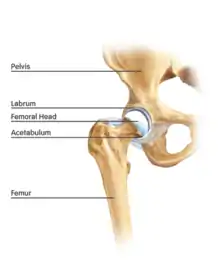

The hip is essentially a ball and socket joint. It consists of the head of the femur (the ball) and the acetabulum (the socket). Both the ball and socket are congruous and covered with hyaline (or articular) cartilage, which allows smooth, almost frictionless gliding between the two surfaces. The edge of the acetabulum is surrounded by the acetabular labrum, a fibrous structure that envelops the femoral head. (See fig. 1) The labrum acts as a seal, or gasket, around the femoral head. However, this is not its only function, as it has been shown to contain nerve endings, which may cause pain if damaged.[18] The blood supply of the labrum has also been demonstrated.[25] The joint itself is encompassed by a thick, fibrous joint capsule, which is lined by synovium. The ligaments that keep the hip joint in place are in fact, thickened areas of joint capsule, rather than distinct structures. The synovium generates fluid that lubricates the joint; in that fluid are the nutrients needed to keep the cartilage cells alive. A total of 27 muscles cross the hip joint, making it a very deep part of the body for arthroscopic access. This is one reason why hip arthroscopy can be quite technically demanding.

The cartilage lining of the socket is in the shape of an inverted horseshoe. The middle of this is termed the cotyloid fossa. Arising from the cotyloid fossa and connecting to the femoral head lies the ligamentum teres. The function of this in the adult is under debate, but in childhood the ligamentum teres carries a blood vessel from the pelvis to the femoral head. This blood vessel usually becomes redundant with age. Arthroscopic hip surgeons are becoming increasingly convinced that the ligamentum teres acts as an internal stabiliser of the hip joint, and pathological injury to the ligament is now a recognised cause of hip pain and instability.[8][26]